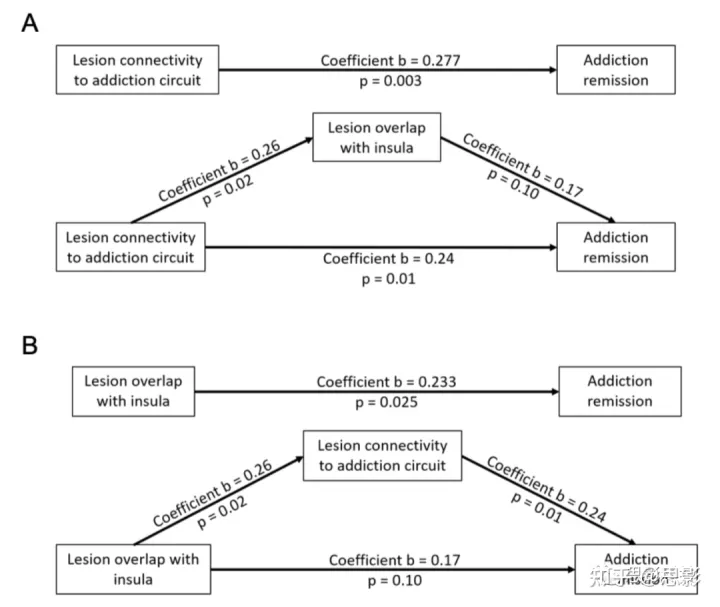

我们进行了中介分析,以测试我们的连通性结果是否由先前报道的病变与岛叶重叠介导(图 S8)。为了保持与原始报告的一致性,我们使用与岛叶的分类交叉(是/否)记录每个病变。接下来,我们使用空间相关性计算每个患者的病变连接性与我们的成瘾缓解图的相似性,使用 Fisher 的 r 到 z 变换转换为正态分布。这导致每个病变都有一个数字,反映病变位置与我们的成瘾缓解网络的连接性。使用 Tor Wager(https://github.com/canlab/MediationToolbox)的 MATLAB 中介工具箱,我们进行了中介分析,其中病变连接性作为主要预测因子,成瘾缓解作为主要结果,岛叶重叠作为中介。我们假设连通性对成瘾缓解的影响不会由岛叶重叠介导。为了完整起见,我们还测试了与成瘾缓解网络的连接是否可能介导先前报道的脑岛损伤与成瘾缓解之间的关联。

图 S8:中介分析。

与岛叶重叠的病变可显著预测成瘾缓解,病变连接性也是如此。然而,病变连通性对成瘾缓解的影响不是由病变与岛叶重叠的影响介导的(A)。然而,之前提到的岛叶损伤和成瘾缓解之间的关联可能是通过与我们成瘾回路的连接来介导的 (B)。